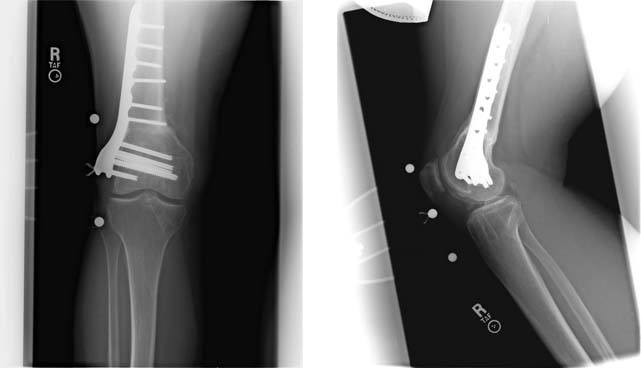

1. These are radiographs of her knee showing minimal arthritis and the presence of the osteotomy plate on the outer aspect of the femur.